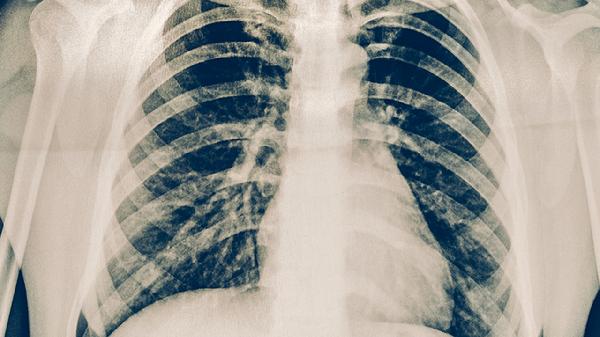

肺心病肺动脉高压形成的主要原因是什么

肺心病肺动脉高压形成的主要原因有慢性阻塞性肺疾病、低氧性肺血管收缩、肺血管重塑、左心疾病及血栓栓塞性因素等。肺心病是慢性肺源性心脏病的简称,其肺动脉高压的形成与肺部疾病和心脏病变密切相关。